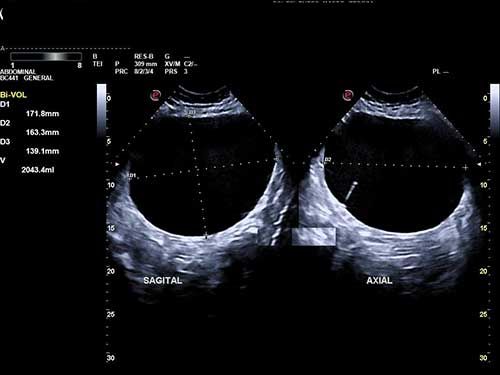

Okay, so the last choice isn't really an option, but you get the picture when it comes to the variety of ultrasound imaging.